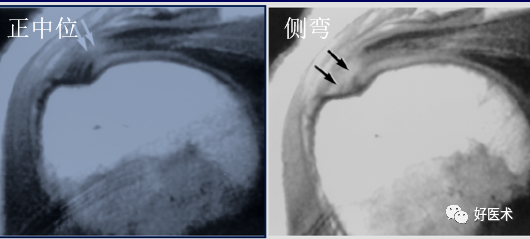

5)MRI表现

肩峰的形状:

-

Ⅰ型:扁平型;

Ⅱ型:弓型;

Ⅲ型:钩型

肩峰下缘倾斜,肌腱撕裂